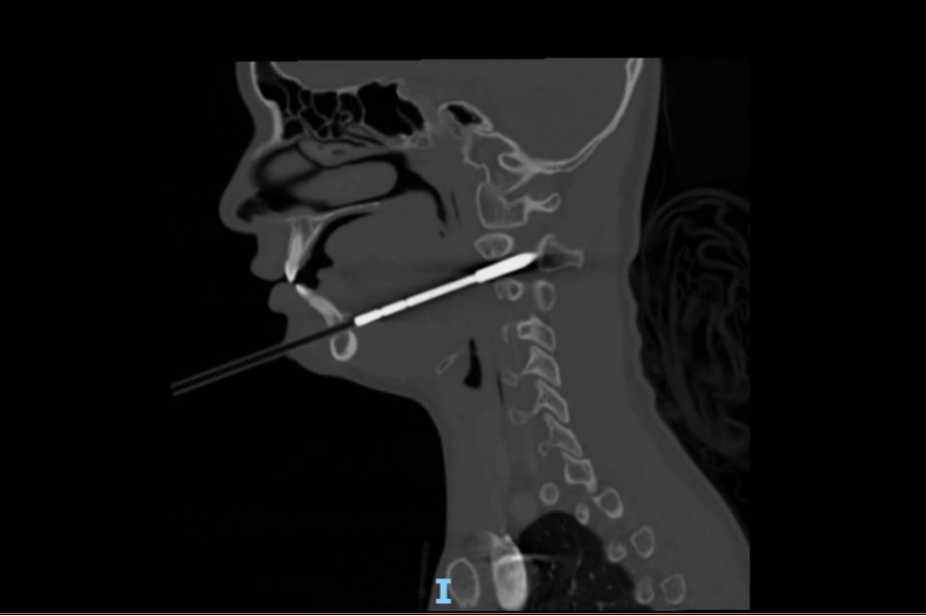

6月2日凌晨,娜娜在父母和教练的陪伴下,紧急抵达北京儿童医院急诊。首诊的急诊内科戴国瑞医师迅速对娜娜的病情进行了全面评估。尽管娜娜的生命体征平稳、神志清楚,肢体活动和感觉也未见异常,但CT影像结果却揭示伤情的复杂性:箭矢穿通了下颌骨和右侧颈2椎体,累及椎管,横突孔内缘骨质可疑受累,且箭头尖段进入椎管长度约12毫米,右侧咽旁间隙受累,局部气道向左侧偏移。

箭矢必须取出,但如何取出才能最大程度降低对孩子的损伤呢?在获得明确的影像学资料后,戴国瑞医生立即将娜娜的情况上报了医务处,在医务处的支持下,迅速牵头组织急诊外科、骨科、口腔科、耳鼻咽喉头颈外科等多学科团队(MDT)进行紧急会诊,快速制定了详细的治疗方案:决定立即手术,实施颌面部异物取出术。